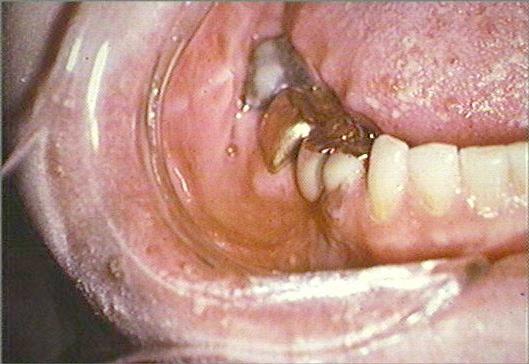

The patient has a toothache involving the mandibular right first and second molars of three days duration. Blisters and painful ulcers on the right side of her face and oral mucosa began this morning. Theoral ulcers bleed when she brushes her teeth. She has not noticed anything which makes the toothache or the lesions better or worse. The patient reports that the skin lesions consist of red areas with blisters on the right side of her face and the oral lesions are present on her tongue and gums.

The skin on the right side of the face is erythematous and contains small vesicles and ulcers. Small ulcers are present on the right dorsum of the tongue, mucobuccal fold and the gingival papilla between the mandibular right central and lateral incisors. The mandibular right first and second molars and the surrounding mucosa are painful to palpation. The periapical radiograph reveals no evidence of periapical disease. The mandibular right first and second molars are responsive to pulp testing and give no evidence of pulpitis. No palpable lymph nodes are present.

close-up of chin close-up of face and tongue

close-up of right mandibular teeth and gingiva